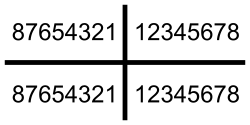

Die Anzahl, die Länge und der Durchmesser der Wurzeln bestimmen zunächst die Grundwertigkeit eines gesunden Pfeilerzahnes. Die Grundwertigkeit wird in drei Klassen eingeteilt:[2]

1 = beste Wertigkeit

2 = mittlere Wertigkeit

3 = eingeschränkte Wertigkeit

| oben rechts | oben links | |||||||||||||||

|---|---|---|---|---|---|---|---|---|---|---|---|---|---|---|---|---|

| 3 | 1 | 1 | 2 | 3 | 1 | 3 | 2 | 2 | 3 | 1 | 3 | 2 | 1 | 1 | 3 | Pfeilerwertigkeit |

| 18 | 17 | 16 | 15 | 14 | 13 | 12 | 11 | 21 | 22 | 23 | 24 | 25 | 26 | 27 | 28 | Zahn- |

| 48 | 47 | 46 | 45 | 44 | 43 | 42 | 41 | 31 | 32 | 33 | 34 | 35 | 36 | 37 | 38 | bezeichnung |

| 3 | 1 | 1 | 2 | 2 | 1 | 3 | 3 | 3 | 3 | 1 | 2 | 2 | 1 | 1 | 3 | Pfeilerwertigkeit |

| unten rechts | unten links | |||||||||||||||

(Incisivi (Schneidezähne), Canini (Eckzähne), Prämolaren (kleine Backenzähne), Molaren (große Backenzähne)).

Beispielsweise sind die Zahnwurzeln der unteren Schneidezähne (32–42) sehr dünn und können deshalb keine so hohen Belastungen tragen wie vergleichsweise die unteren Eckzähne (33, 43), die längere und dickere Wurzeln aufweisen.